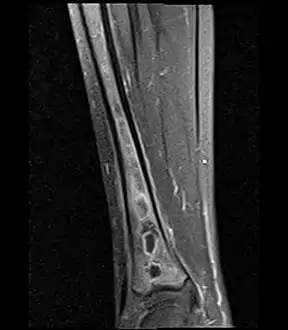

Fat saturated STIR (short tau inversion recovery) image showing hyperintense edema in the calf musculature, marrow edema, and subperiosteal pus. The intramedullary abscess cavity is hyperintense as well.

Coronal fat suppressed STIR image showing, bone marrow and subcutaneous edema as well as subperiosteal edema. The thin hypointense rim surrounding the intramedullary collection represents the reactive interface between the abscess and the body's attempt to wall it off.